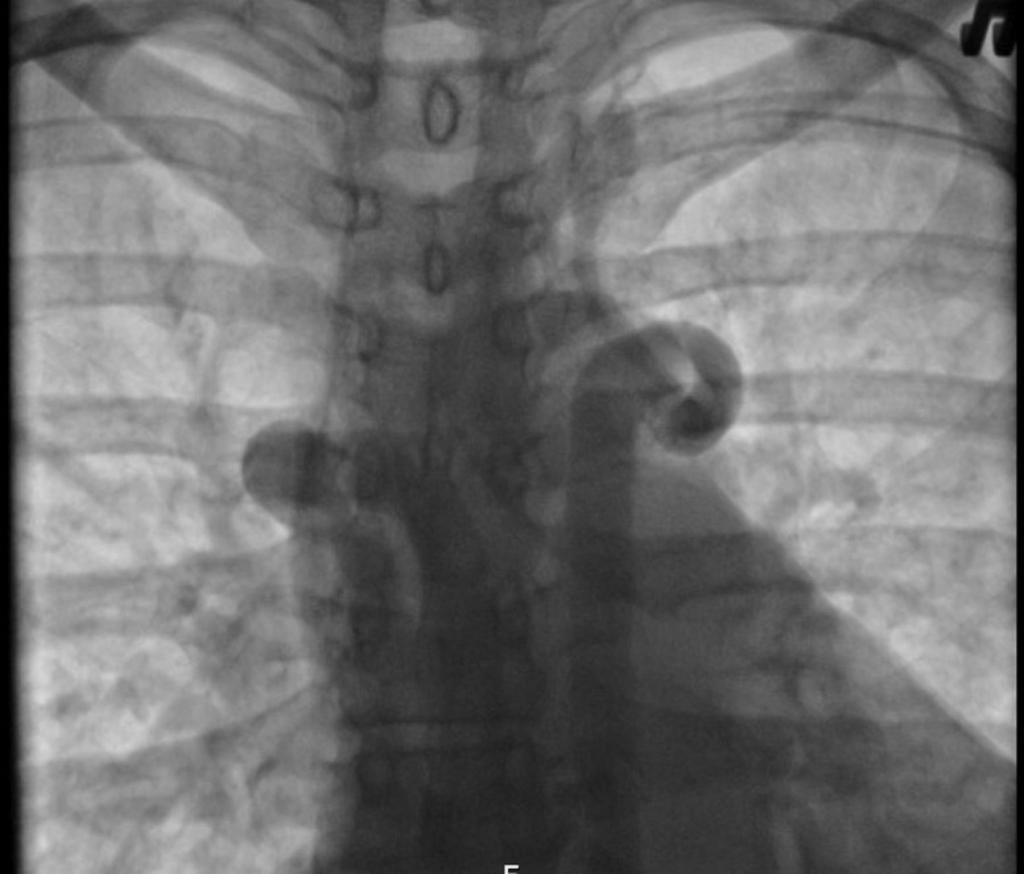

При рентгеновском излучении лёгких, поражённых коронавирусной инфекцией, наблюдаются затемнения в нижней части органа (на снимке обозначаются белыми пятнами). Пятна называются симптомом “матового стекла”. На рентгене видны пятна, которые обуславливаются наличием жидкости в лёгких.

Симптом “матового стекла” в легких

Симптом “матового стекла” проявляется у больных на фоне поражения лёгких вирусом. Так как дыхательный орган подвергается серьёзным изменениям, в нём появляются зоны повреждений.

Снижается плотность лёгочной ткани. В поражённом участке проявляется умеренно-сниженная воздушность, главным признаком выступает видимость сосудов лёгких и стенок бронхов.

Заметить данный симптом на рентгене сложно, поэтому требуется дополнительно сделать компьютерную томографию.

Типичные признаки проявления симптома “матового стекла”:

- стенки и структура бронхов чётко проглядываются;

- видны затемнения;

- сохраняется сосудистый рисунок;

- повышается прозрачность лёгочной ткани.

Ниже представлены фото, как выглядит симптом “матового стекла” на рентгене и компьютерной томографии: